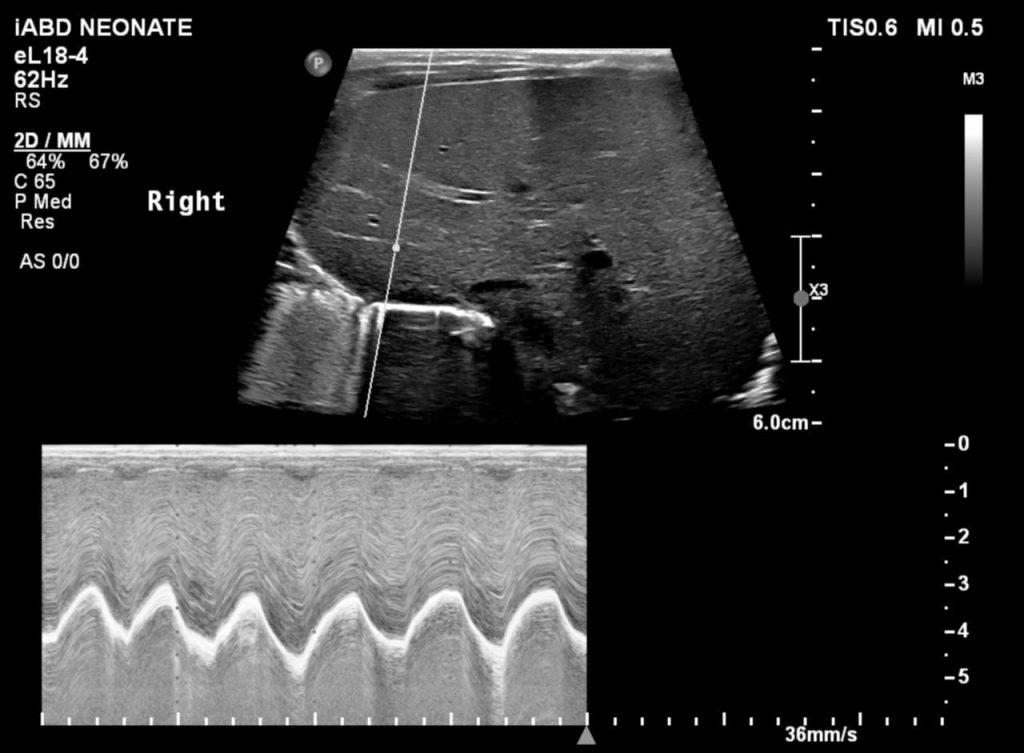

Figura 1: Diafragm drept cu mișcare normală la ultrasonografie.

Ecografia este un bun înlocuitor pentru fluoroscopia și poate fi efectuată la pat cu pacientul întins, dacă poate respira în această poziție. Este mai ușor să evaluezi copiii cu ultrasunete cu evitarea riscul de iradiere. Ecografia în timp real este efectuată în plan axial pentru a compara cele două hemidiafragme simultan. Modul M suplimentar coronal sau sagital poate ajuta la cuantificarea gradului de mișcare a fiecărui hemidiafragm individual. Criteriile de diagnostic la copii includ mișcarea paradoxală, excursia mai mică de 4 mm și o diferență >50% între excursia unui hemidiafragm față de celălalt.